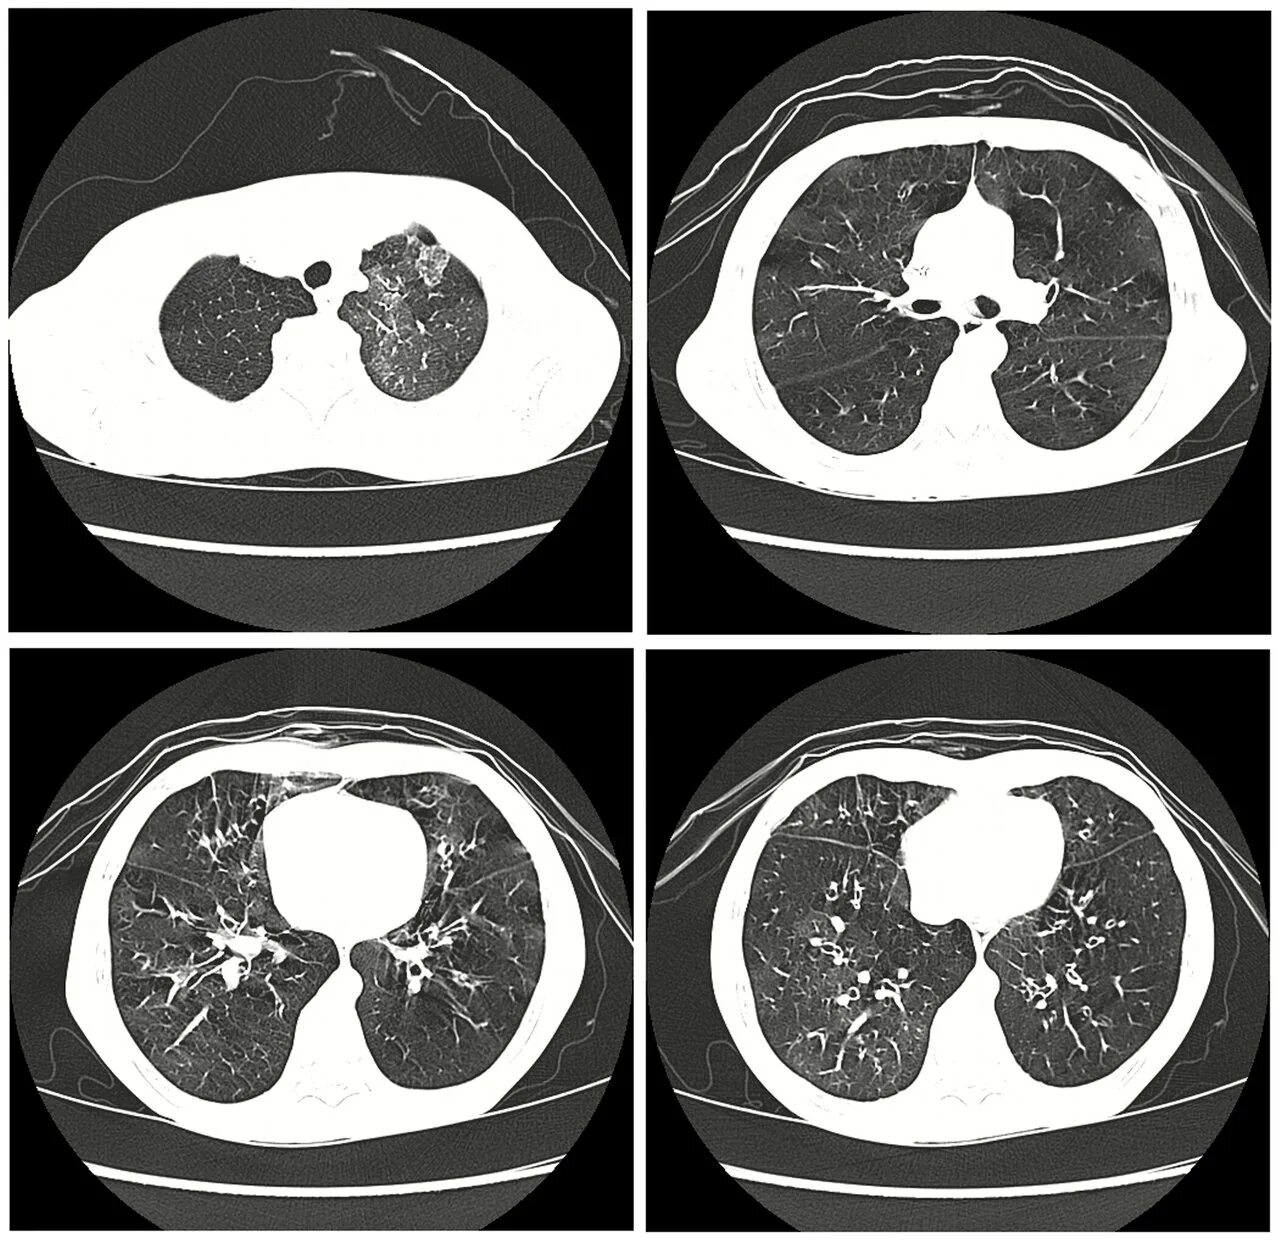

Утолщение бронха